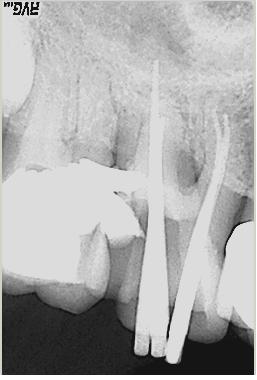

Röntgenologischer Ausgangsbefund im Febr. 2003 mit caries profunda, starken Krümmungen sowohl der mesiobuccalen wie auch der distobuccalen Wurzeln

Zustand unmittelbar vor Behandlungsbeginn im Juni 2003. Die Fraktur des distalen Zahnanteils hat die Patientin jetzt zur Einwilligung in die Behandlung motiviert. Auffällig ist in dieser Projektion die besonders starke Krümmung der mb Wurzel sowie die knochennahe Defektlage distal. Es erfolgte zunächst die Kariesentfernung gefolgt von einer chirurgischen Kronenverlängerung zur Herstellung der biologischen Breite sowie Ermöglichung des sog. Ferrule-Effektes. Danach wurde der Zahn adhäsiv aufgebaut. Erst jetzt wurde mit der eigentlichen WKB begonnen